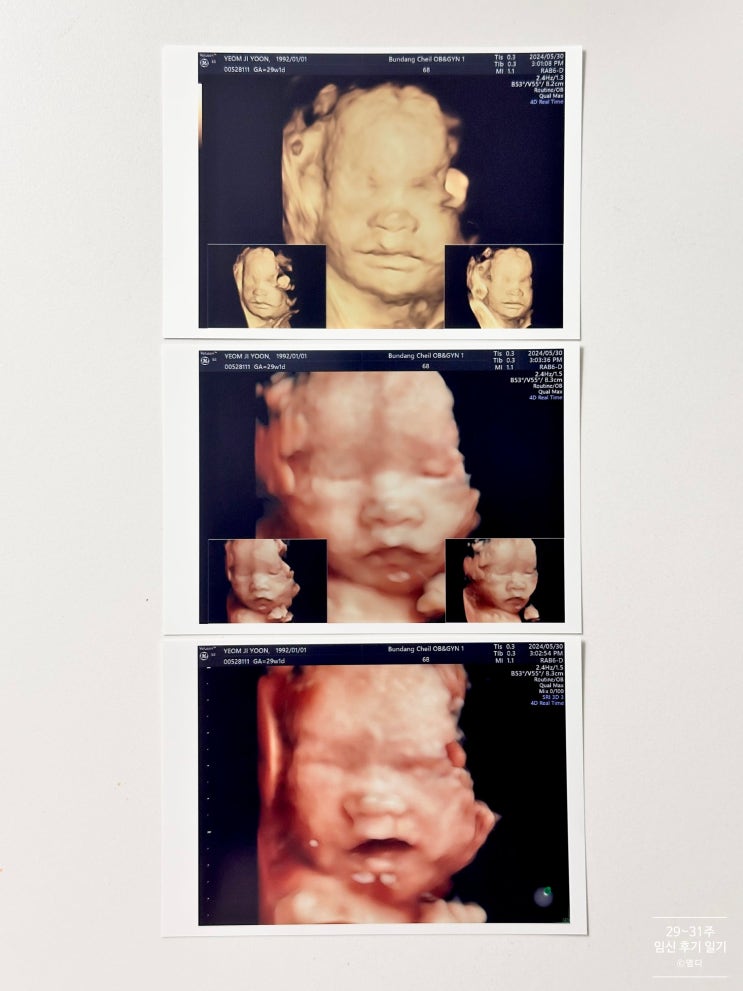

29~31주 8개월차 후기임산부 입체초음파 태교 당근 세탁 만삭사진 찍으며 바쁜일상

29주차 5월 29일 ~ 6월 4일 시간 잘가고 아기는 무럭무럭 크고!0! 아직 숨이 많이 차는 단계는 아니지만 전...